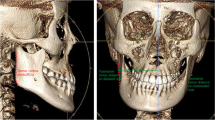

All subjects had CBCT scans (Philips MX 16-slice) taken in maximum intercuspation, which were obtained at 90 kV and 40 mA with a slice thickness of 0.49 mm. Digital Imaging and Communications in Medicine (DICOM) files obtained from the CBCT scans were reconstructed using Dolphin 3D (Dolphin Imaging, version 11.7, Chatsworth, CA91311, USA) software. Reorientation of each scan was performed using the standardized 3D reference planes. The landmarks, measurements, and reference planes selected for this investigation were shown in Figs. 1, 2, and 3. The following reference planes were used to ensure the consistent orientation of the 2D cross-sectional slices: (1) Frankfort horizontal (FH) plane: plane passing through right porion, left porion, and midpoint of left and right orbitale, (2) midsagittal plane (MSP): plane perpendicular to FH plane, passing through the neck of the crista galli and Opisthion, (3) coronal plane: plane perpendicular to FH plane and MSP, passing through Op.

Skeletal analysis

On the coronal view, the jugal process (J) and antegonial (Ag) widths on each side were assessed relative to MSP. The sum of both sides represented the total width of the maxilla (J–J) and mandible (Ag–Ag) respectively. The maxillomandibular width difference was calculated by subtracting the total maxillary width with the total mandibular width [(J–J) − (Ag–Ag)] (Fig. 1A). Menton (Me) deviation was measured relative to MSP to indicate mandibular displacement. The corpus length of the mandible was measured for both sides from the most posterior point of the gonial angle, gonion posterius (Gopost) to the menton (Me) on the axial view (Fig. 1B).

Maxillary vertical assessments were investigated by measuring the distance from the jugal process to the FH plane (J-FH) (Fig. 1A). The vertical assessments of the mandible were made according to Habets’ technique [19] and made separately for both sides on the sagittal view of the CBCT image. The most posterior points on the condyle and ramus were marked as A1 and A2, respectively. A line that passed through points A1 and A2 were termed the A-line. A second line drawn from the most superior point of the condylar (Co) and perpendicular to the A-line, was termed the B-line. The intersection of the A- and B-line was called point Z. The distances between points A1 and Z were measured as condylar height (CH). Similarly, the distances between points A1 and A2 were measured as ramus height (RH), and the distances between points Z and A2 were measured as condylar plus ramus heights (CH + RH) (Fig. 1C). The asymmetry index [19] of condylar height (CAI), ramal height (RAI), and condylar plus ramal height (CRAI) were calculated based on the following formula: